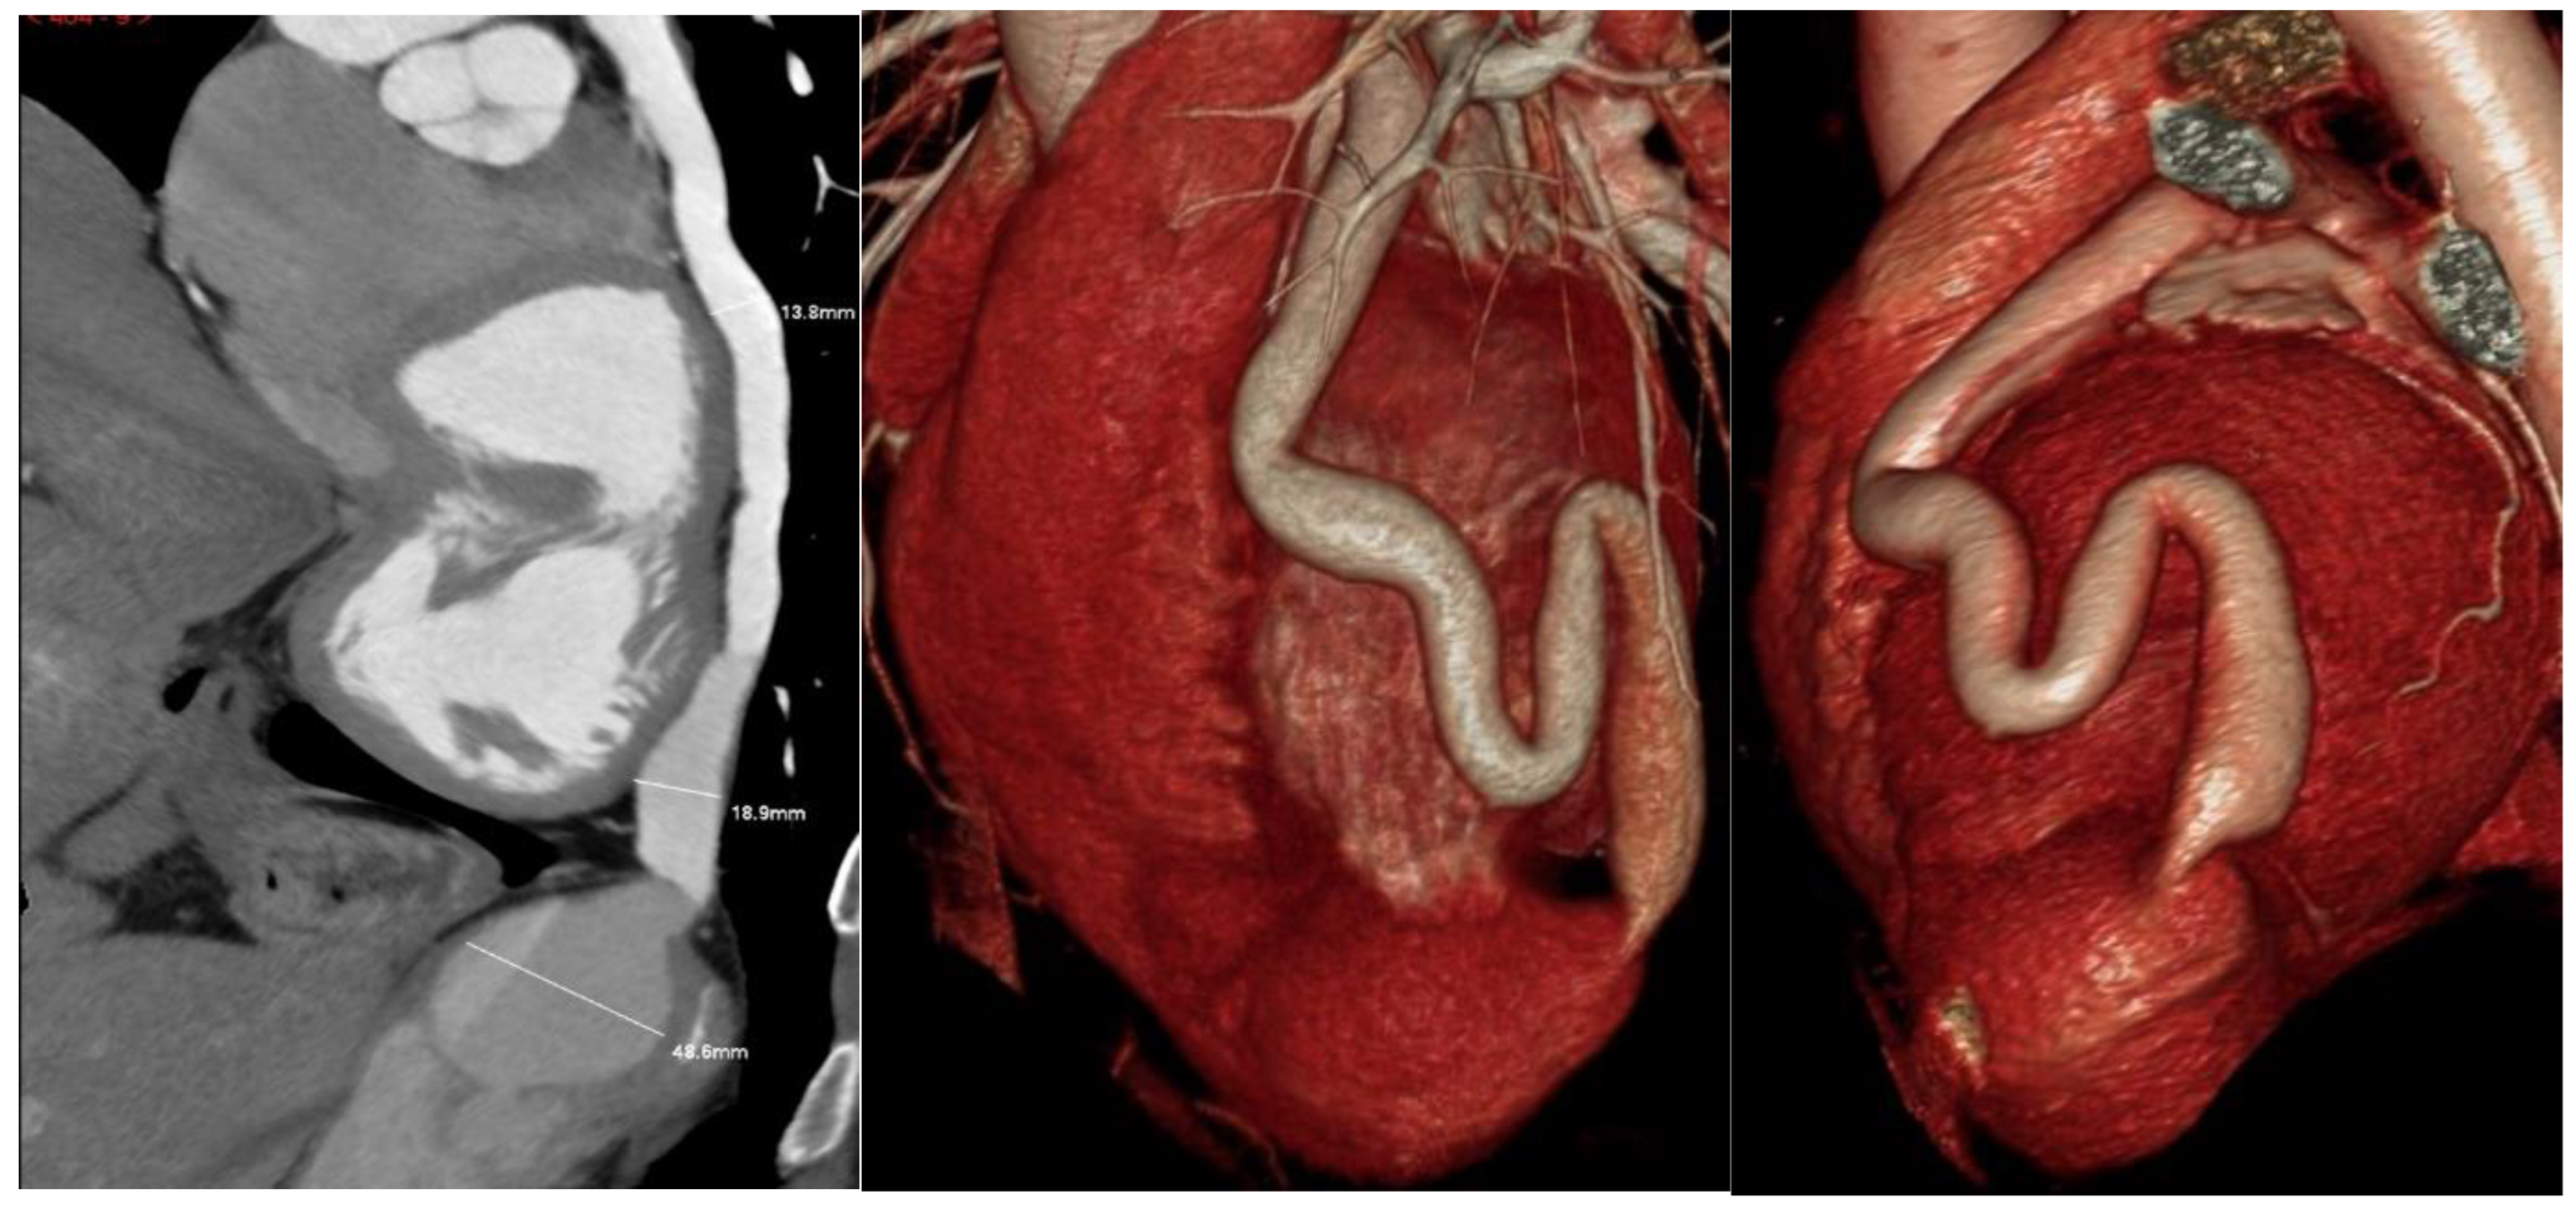

2. Case Presentation